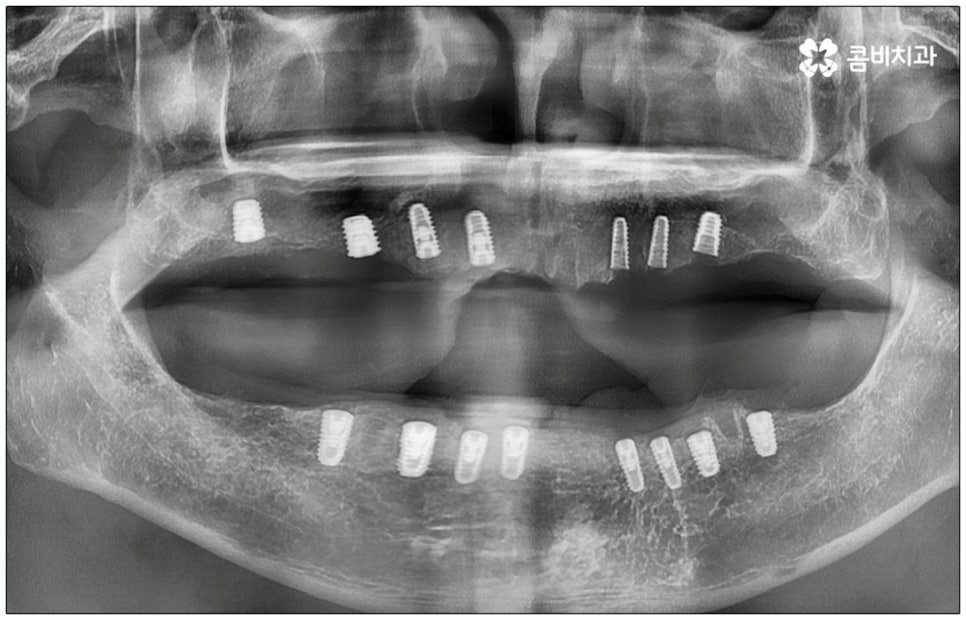

전신 질환을 앓고 있는 분들이나 고령의 환자분들, 다수의 임플란트가 필요한 분들의 경우 컴퓨터 분석을 활용한 임플란트 방식을 통해 도움받아 볼 수 있는데요. 네비게이션 임플란트라고 불리는 이 방식은 첨단 장비를 통해 육안으로 확인하기 어려운 구강 내부의 골조직, 신경 등의 해부학적 구조를 살펴본 다음 3D 모의 수술을 통해 최적의 수술 경로를 찾아내어 가이드를 제작하고 이를 장착하여 그대로 진행하기 때문에 보다 정확하고 안전하게 노인임플란트 수술을 진행할 수 있습니다.

이러한 네비게이션 임플란트 방식은 디지털 기술로 위험 요소를 사전 분석하여 식립 위치와 각도를 보다 정교하게 예측하기 때문에 임플란트 부작용의 발생률을 낮추고 식립 안정성을 높일 수 있는데요. 무절개 또는 최소절개 수술이기 때문에 시술 시간이 짧고 통증이 적으며 회복 기간이 빠르다는 장점을 가지고 있으나 정밀 검진 후 상황상 골유착 과정의 안정성이 떨어질 수 있는 케이스의 경우에는 절개 및 개방 후 수술을 진행하는 것이 좀 더 유리하기 때문에 꼼꼼한 검진, 정확한 판단, 의료진의 높은 숙련도가 굉장히 중요하다고 할 수 있어요.

특히 다수의 치아를 상실했을 때 전체적인 교합, 골조직 및 잇몸 상태, 얼굴형과의 조화 등 모든 부분을 종합적으로 고려하여야 하며 노인임플란트 수술의 경우 다양한 변수가 발생할 수 있기 때문에 이러한 고난도 임플란트 케이스에 노련하게 대처할 수 있도록 풍부한 임상 경험과 노하우를 갖춘 의료진인지, 정밀 검진 기계를 보유하고 있는지, 처음부터 끝까지 철저한 케어 시스템을 갖추고 사후 관리까지 꼼꼼하게 진행하는지 등을 잘 살펴보시고 임플란트 수술을 진행할 치과를 신중하게 선택하시길 권유드리고 있습니다.